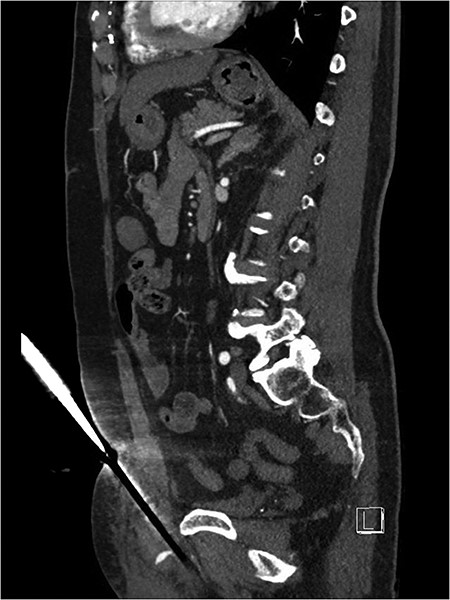

Suprapubic stab wound: sagittal section: CT mesenteric angiogram showing knife directed in infero-posterior direction abutting but not traversing the peritoneum. Active arterial contrast extravasation can be seen. The tip of the knife abuts the root of the penis.

After discussion with urology, a 14Fr indwelling catheter was inserted, which drained yellow urine. A computed tomography (CT) mesenteric angiogram demonstrated penetrating injury to the suprapubic region with haematoma and two foci of arterial extravasation with radiological evidence of peritoneal breach, and the metallic foreign body in situ (Figs 2 and 3). Importantly, the tip of the knife appeared to end at the base of the penis at the expected confluence of the dorsal vein.